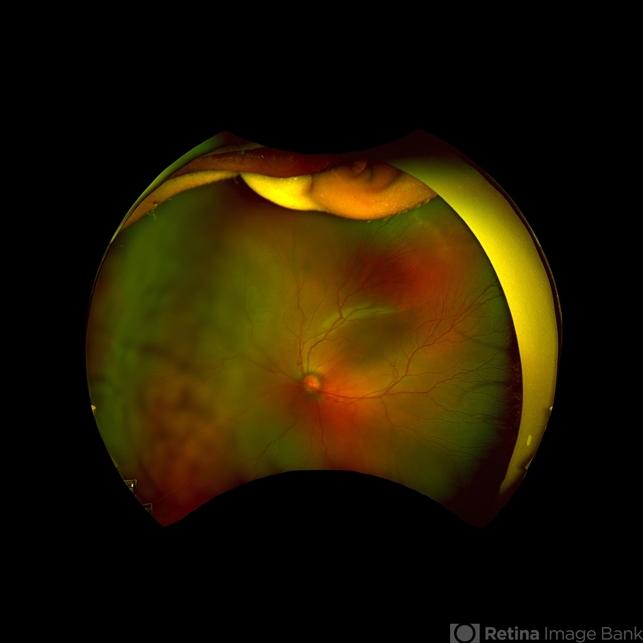

- retinopathy of prematurity (ROP)

- Scanning laser ophthalmoscope

- 7-month-old male with improving ROP.